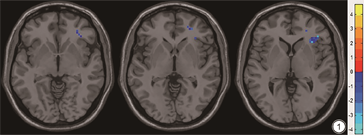

与VR治疗前比较,治疗后VM患者右侧部分额叶及岛叶ALFF值明显降低,差异具有统计学意义(GRF校正:P<0.001,表2;图1)。此外,相关性分析显示,经过VR治疗后的VM患者DHI评分与右侧岛叶ALFF值呈正相关(r=0.549,P<0.05,未校正;图2)。VM患者的其他临床特征与右侧岛叶活动无显著相关性(HAMA:r=-0.166,P>0.05;HDMD:r=-0.251,P>0.05)。

前庭性偏头痛(VM)患者前庭康复(VR)前后低频振幅(ALFF)差异显著的脑区

Brain regions with significant ALFF differences between VM patients before and after VR

| 脑区 | MNI坐标 | t值 | P值 | ||

|---|---|---|---|---|---|

| x | y | z | |||

| Insula_R | 33 | 24 | 3 | -4.19 | <0.05 |

| Frontal_Inf_Tri_R | 38 | 30 | 3 | -4.14 | <0.05 |

注:MNI(Montreal Neurological Institute):蒙特利尔神经病学研究所;Insula_R :右侧岛叶;Frontal_Inf_Tri_R:右侧额下回三角部。